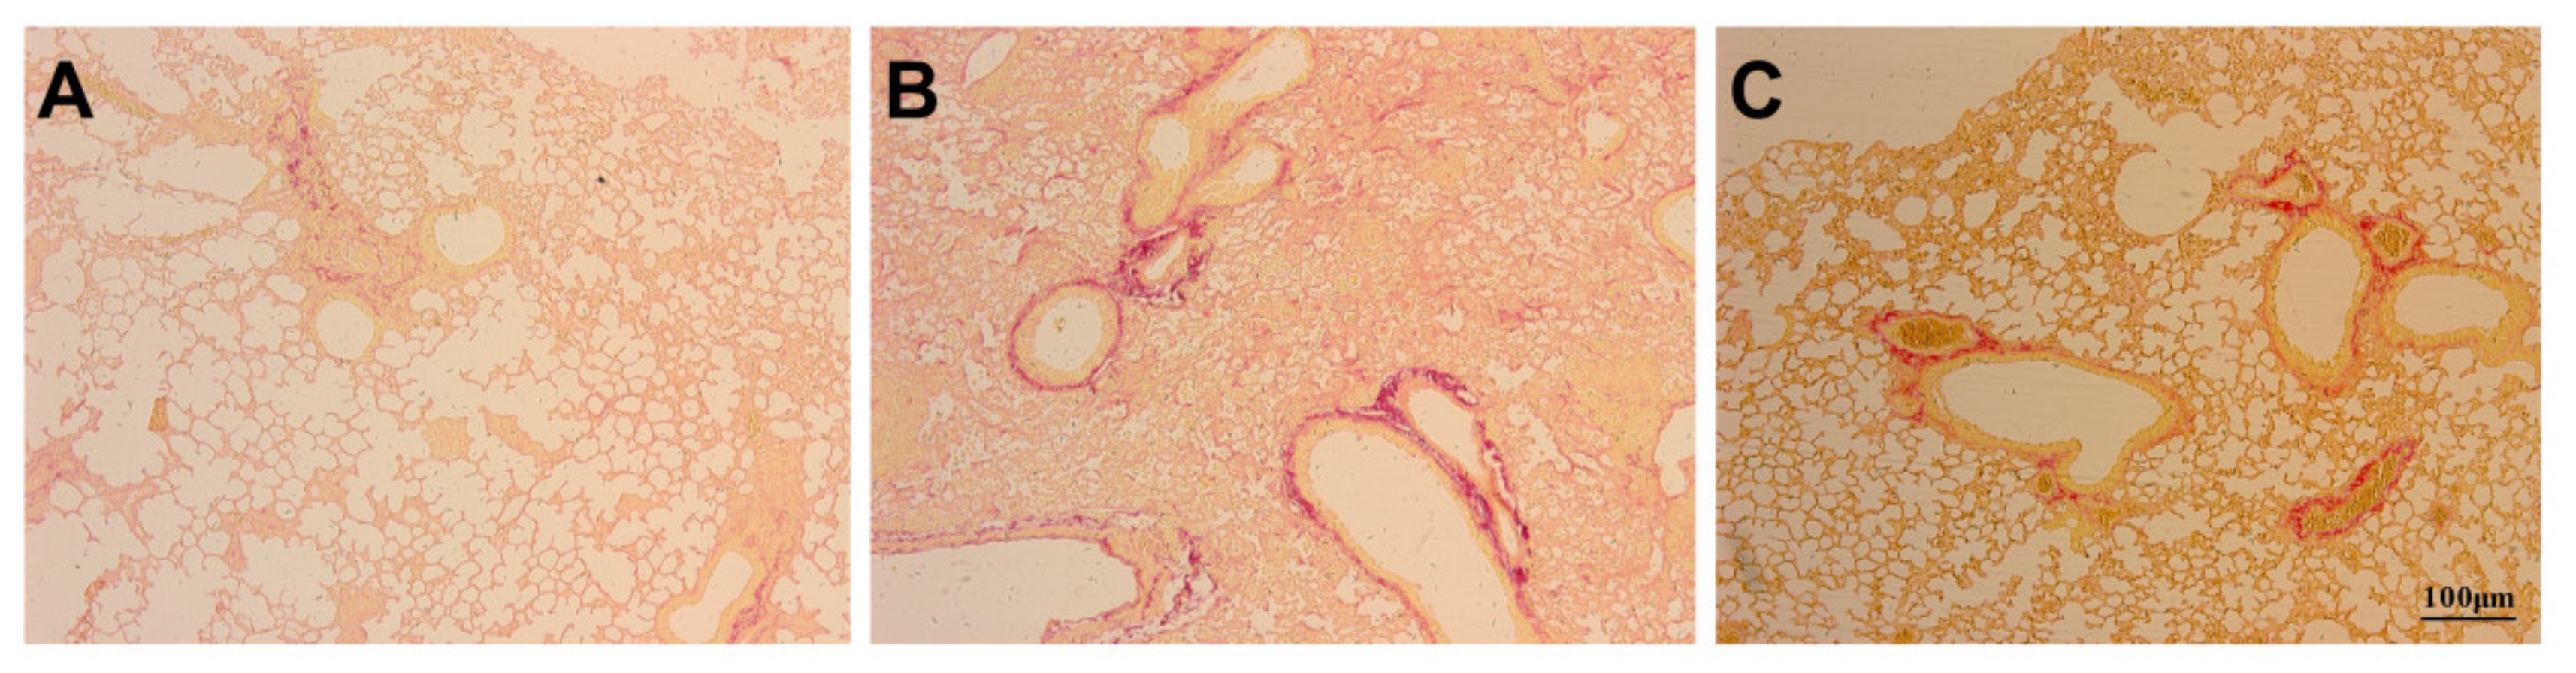

3.4. Assessment of Apoptosis